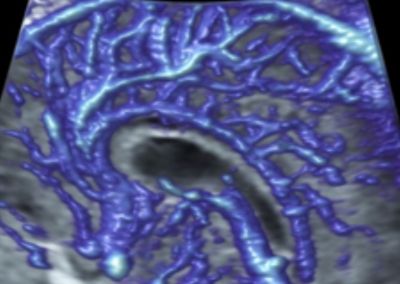

L’Université Paris Cité franchit une nouvelle étape dans le domaine de l’imagerie médicale anténatale avec l’acquisition d’un système d’Imagerie par Résonance Magnétique (IRM) 1,5T ARTIST™ de GE HealthCare. Cet équipement de pointe renforce les capacités de la Plateforme LUMIERE à l’hôpital Necker-Enfants malades, plateforme intégrée de soins, de recherche clinique et d’enseignement en imagerie médicale de la femme enceinte, du fœtus et du placenta.

Une plateforme au service de la recherche et des patientes enceintes

En soutenant des vocations scientifiques et en accompagnant celles et ceux qui construisent la recherche de demain, la Plateforme LUMIERE contribue activement à l’enrichissement des connaissances sur le développement fœtal et placentaire.